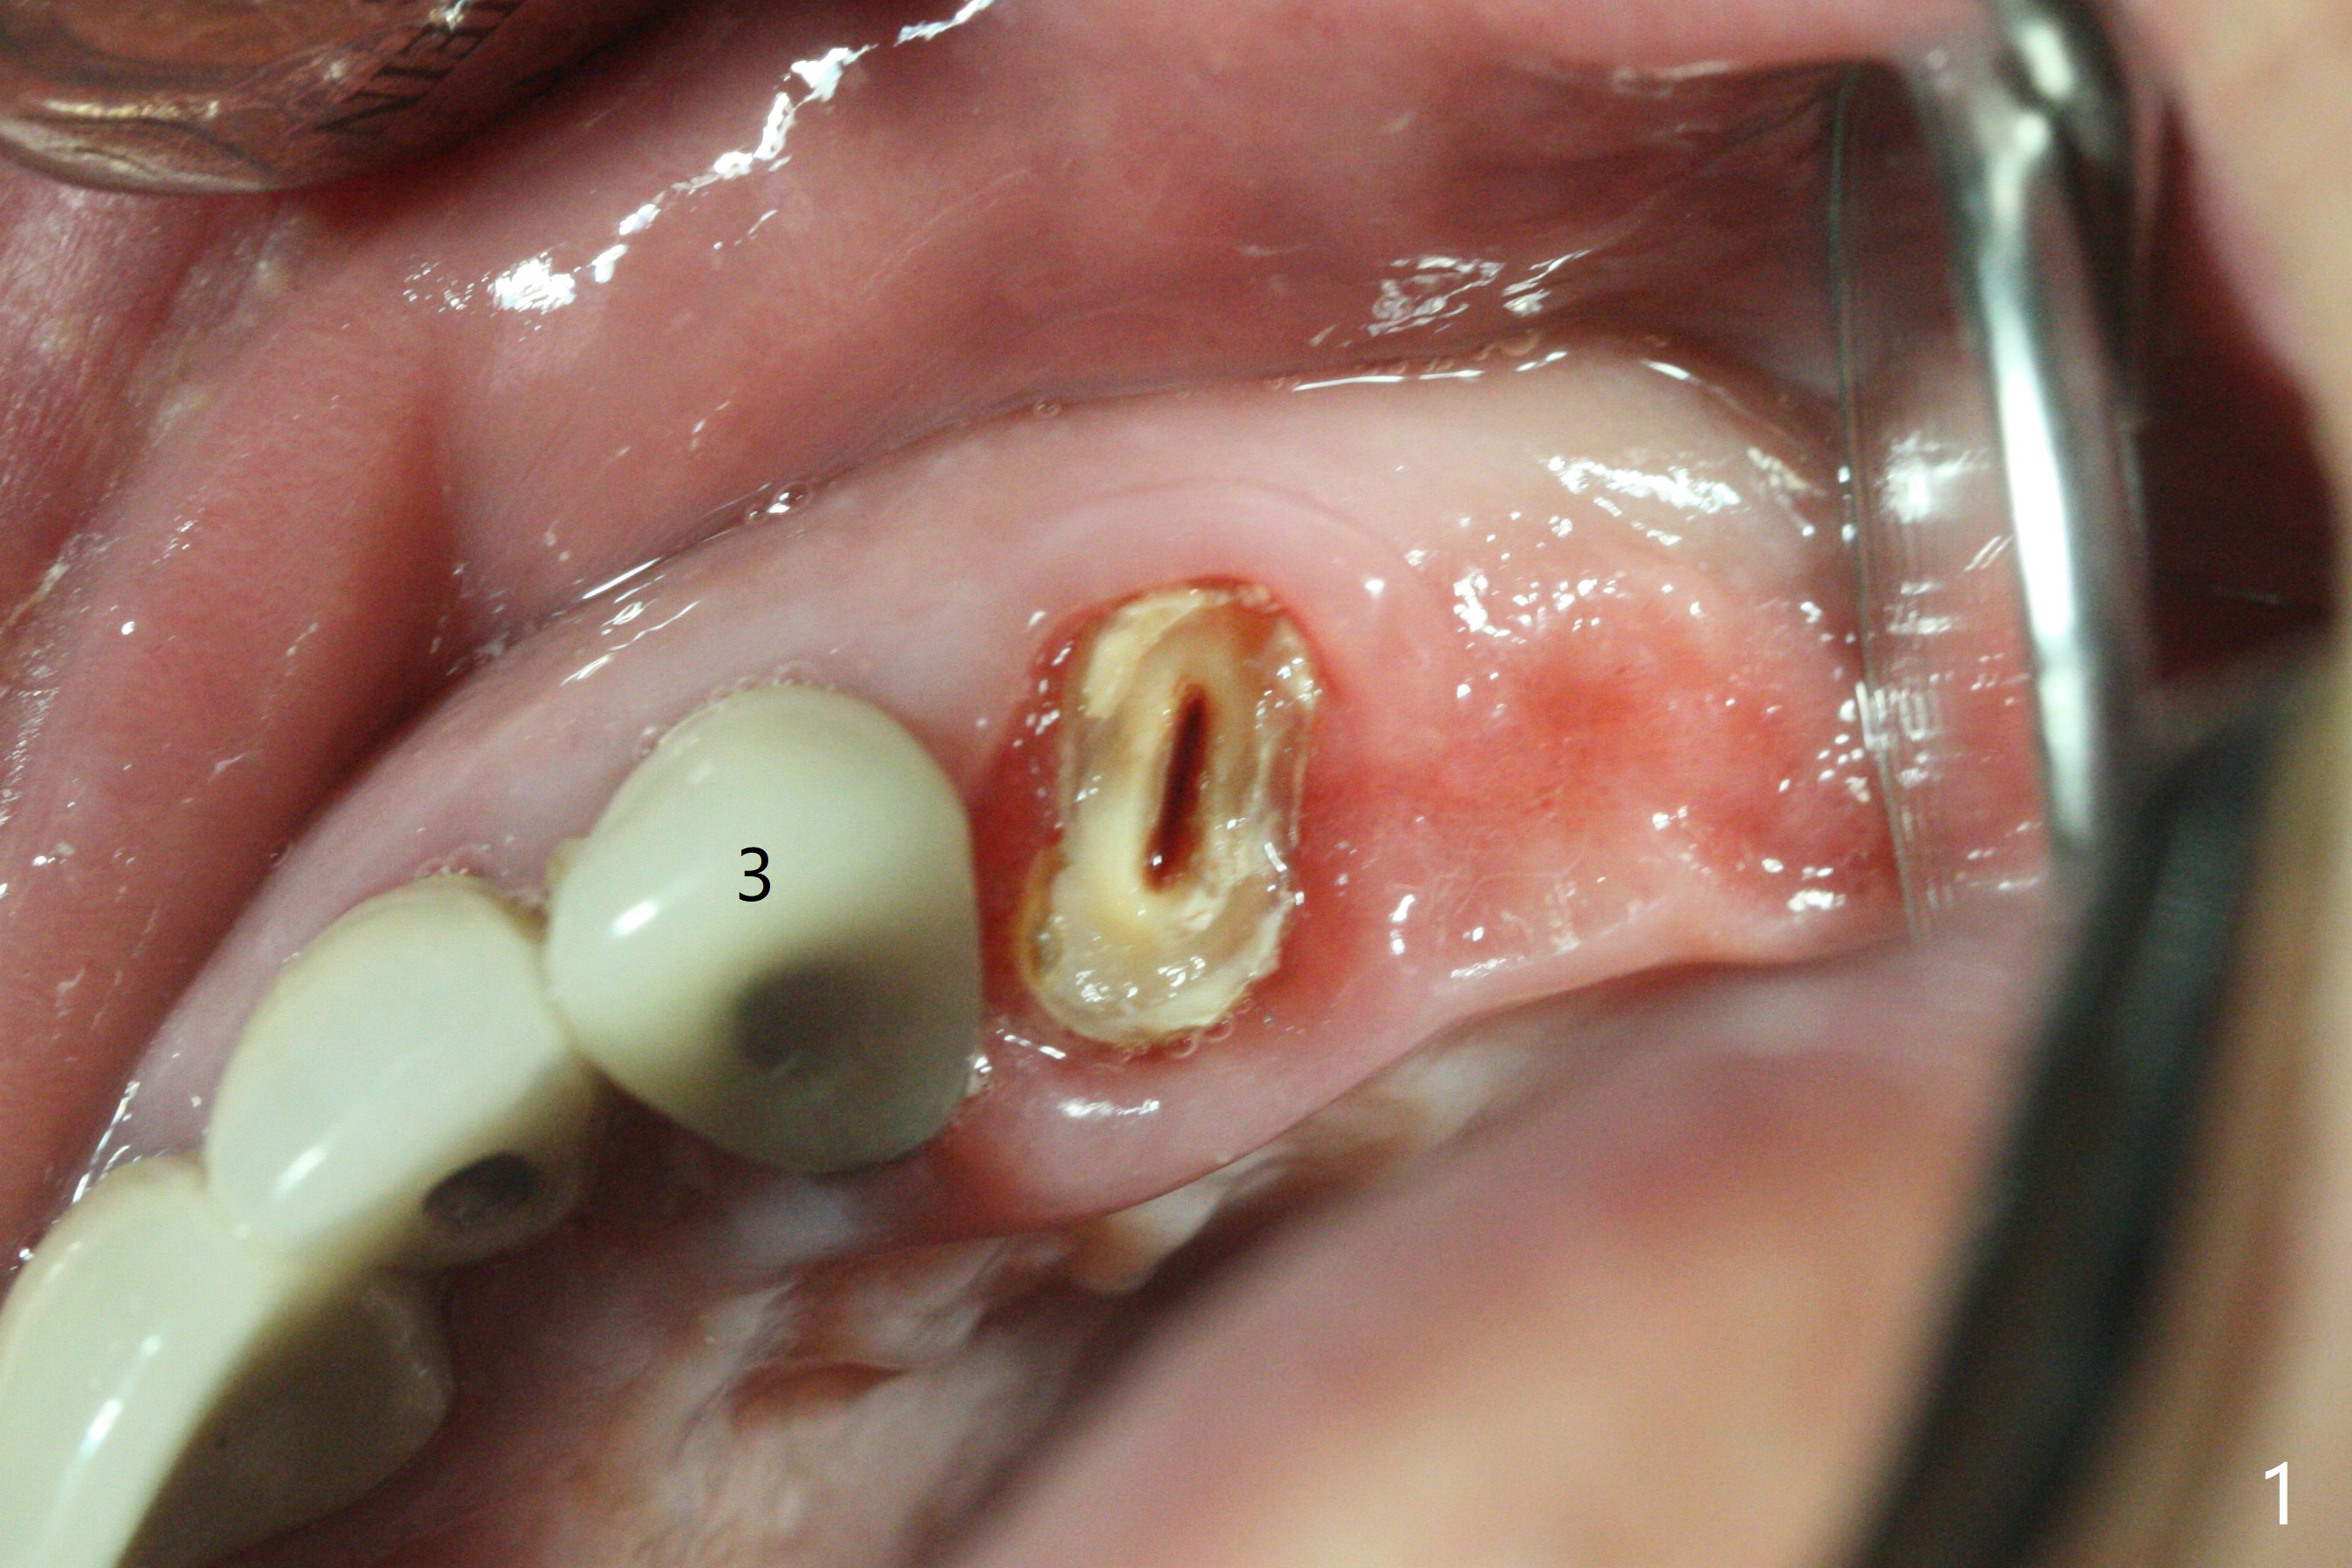

为了美观,病人希望先进行下颌治疗,当他回来时,提到左上肿胀,但是没有明显疼痛。去除左上4-8桥,发现4仍可以保留(图一,二),8龋齿龈下(图三)。4根管治疗只发现颊侧根管(图四:B),腭侧根管好像闭锁,与CT一致。放置氢氧化钙糊剂,明天病人回来治疗,术后两周。我的疑问是,如果肿胀消失,仅完成颊侧根管充填,治疗够吗?什么时候可以安置球状牙桩?如果肿胀没有消失,怎么搞通腭侧根管?